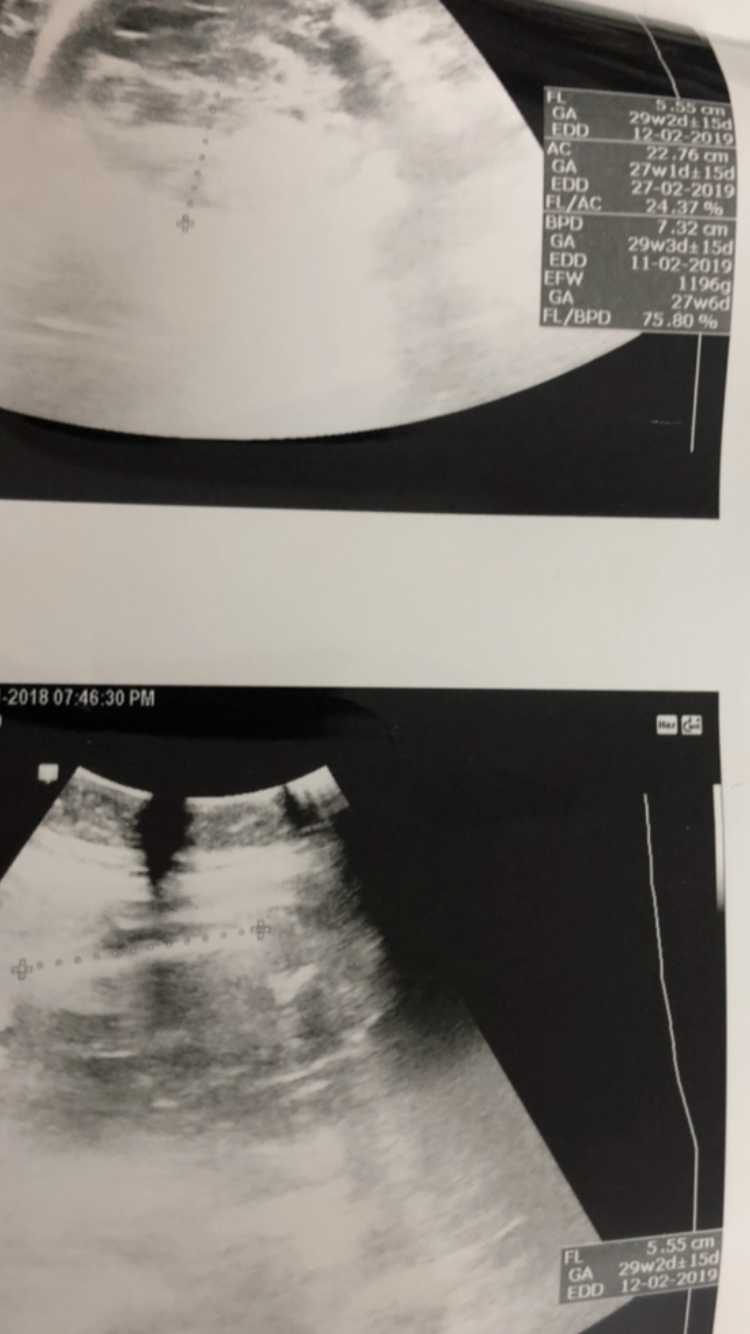

بنات هذا سوناري قبل ٥ايام

محيرني

عند دكتوره جديده

ابغ اعرف كم لي بظبط كانت تقول ماشي ٢٨

اسبوع

لكن اشوف مكتوب ٢٩

🎗سوال ثاني🎗مانوع السونار هذا